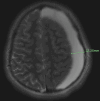

Post-concussion syndrome (PCS) is a common sequela of mild traumatic brain injury in adolescent athletes, typically resolving within weeks. However, persistent or atypical symptoms warrant further investigation to exclude structural pathology. Arachnoid cysts, though often incidental, can become symptomatic following trauma and may mimic or exacerbate PCS. A previously healthy adolescent American football player presented with persistent headaches and cognitive symptoms 14 weeks after a sports-related concussion. Despite completing a return-to-play protocol, his symptoms worsened. A brain MRI revealed a large left-sided arachnoid cyst with a 5 mm midline shift, consistent with a primary arachnoid cyst. The patient was admitted to the medical unit of the pediatric hospital for monitoring on the medical floor with 48 hours of observation and repeat imaging to verify that the MRI findings were not worsening. Serial imaging over three months demonstrated regression of the cyst and resolution of mass effect. He remained asymptomatic at follow-up but was permanently restricted from contact sports. This case underscores the importance of considering structural brain lesions in athletes with prolonged or atypical post-concussive symptoms. MRI played a critical role in identifying a potentially life-threatening condition that mimicked PCS. Conservative management may be appropriate in select cases of arachnoid cysts with favorable clinical and radiographic progression. Surgical management may be necessary in cases of increased intracranial pressure, neurologic deficit, or radiographic progression.